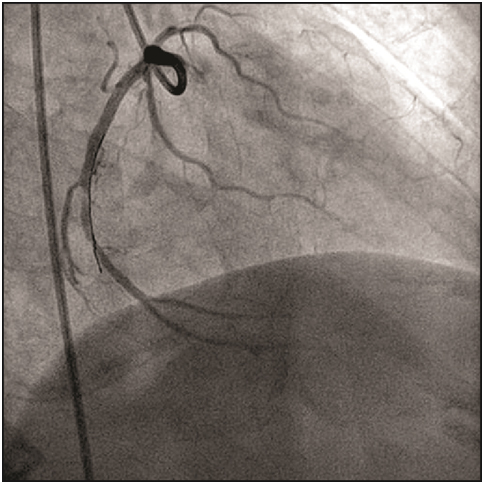

A 7F Judkins guiding catheter (Cordis Corp., Florida, USA) was used to cannulate the left coronary artery, and the lesion was crossed by using 0.014”Floppy guidewire (Abbott Vascular Inc., California, USA). We experienced that the movement of the wire tip became restricted after it crossed, the lesion. Angiograms in different views showed that the distal tip of wire was trapped in a small branch of the left circumflex coronary artery [Table/Fig-1], which had gone into spasm. Immediately, nitroglycerin, sodium nitroprusside, and nicorandil were given to relieve the spasm. Repeated attempts were made to gently pull the wire, but the guiding catheter was getting sucked in to the left circumflex coronary artery and also the guidewire did not move at all. Later, the spring over the wire got uncoiled [Table/Fig-2] and the radio-opaque tip got fragmented upon increasing the pressure over the wire. The two portions were being held together by the fine uncoiled spring coating. At that point, we passed a noncompliant Sprinter balloon (Medtronic Inc., Minnesota, USA) of 1.5 X 10 mm size to the distal tip of the wire and tried to pull the wire gently, but this caused further uncoiling of the wire and the wire could not be retrieved. To tide over the crisis, we used a simple indigenous way of retrieval using a bare noncompliant balloon of 2.5X 9 mm size, which was passed up to the tip of guiding catheter [Table/Fig-3]. The balloon was inflated at 10 atm pressure inside the tip of guiding catheter, which led to successful entrapment of the guidewire between outer surface of the balloon and inner wall of the guiding catheter. Once the wire was secured properly, whole assembly was removed en masse through the vascular system [Table/Fig-4,5 and 6].

Guidewire entrapped in a small branch of the left circumflex coronary artery